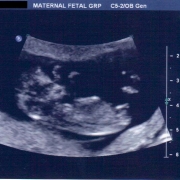

Hello,

I am an Obstetrician & Gynecologist practicing in Colorado Springs. I’ve been delivering babies since 2000, first as a board certified Family Physician and later as a board certified Obstetrician / Gynecologist. I’m a fellow of the American College of Obstetricians and Gynecologists and board certified by the American Board of Obstetrics and Gynecology.

I specialize in full scope obstetrics from minimal intervention birth to high risk pregnancies. My philosophy is that pregnancy is never “one size fits all.” Every patient is unique and I tailor each of my patients’ prenatal plans to specifically meet not only their specific medical needs, but also align their care to try to meet their intended birth plan.